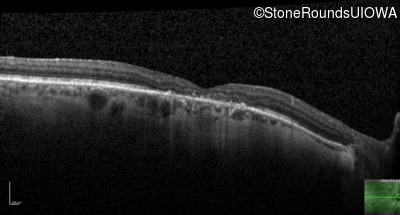

This 52 year old man had normal vision until his mid 30's when he began to have trouble distinguishing colors. the issuing 10 years he had a gradual loss of visual acuity accompanied by increasing photophobia.

| Age at visit: 55 years |

| Age at visit: 58 years |

| Age at visit: 61 years |

| Age at visit: 64 years |